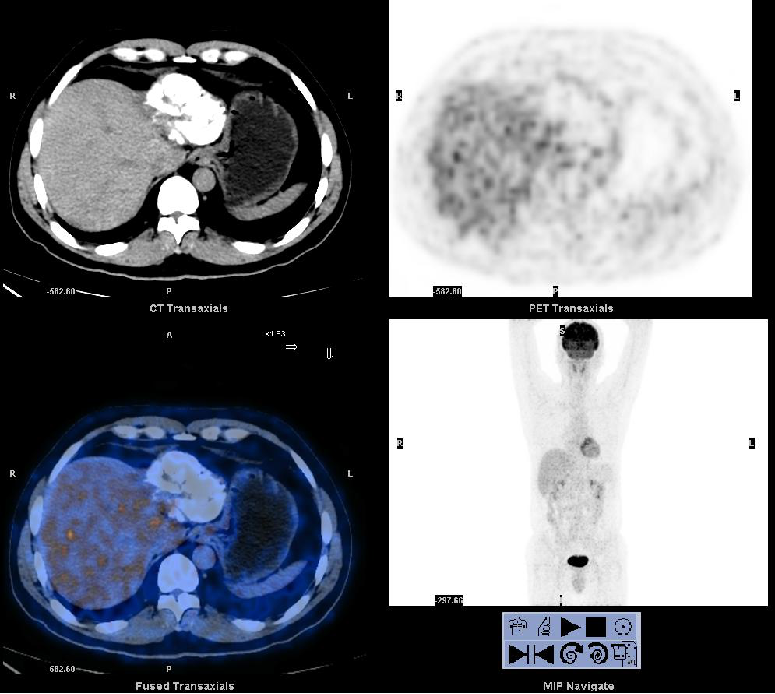

2012-02-22(第二次消融后2个月)复查PET/CT:肝脏病灶代谢未见异常。AFP:3.52 ng/ml。

2012-06-29(第二次消融)后6个月 复查PET/CT:肝脏病灶代谢未见异常。AFP:2.74 ng/ml。

PET/CT在肝癌疗效评价中的作用:

无论是碘油沉积区还是非碘油沉积区都可能有残留病灶存在。

PET/CT对介入治疗后的残留病灶探测具有较高的灵敏度,可以用于介入治疗后的疗效评价。

其对判断肿瘤残留及指导消融治疗较增强CT检查具有更大的优势。